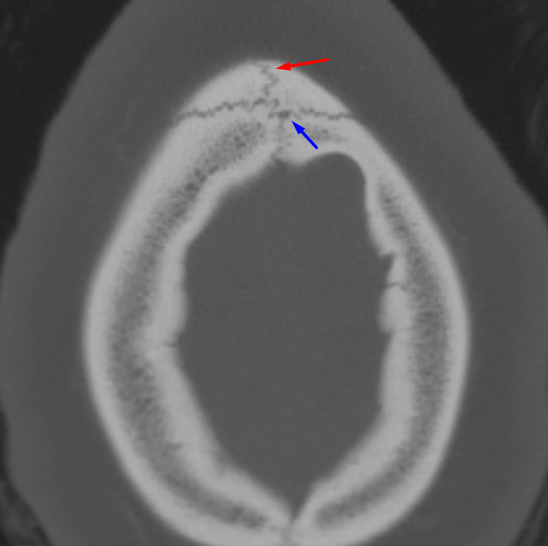

Age: 16

Sex: Male

Indication: Trauma